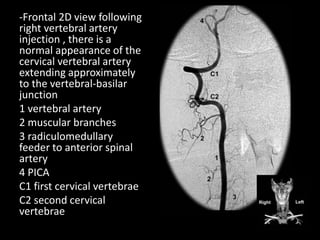

-Frontal 2D view following

right vertebral artery

injection , there is a

normal appearance of the

cervical vertebral artery

extending approximately

to the vertebral-basilar

junction

1 vertebral artery

2 muscular branches

3 radiculomedullary

feeder to anterior spinal

artery

4 PICA

C1 first cervical vertebrae

C2 second cervical

vertebrae